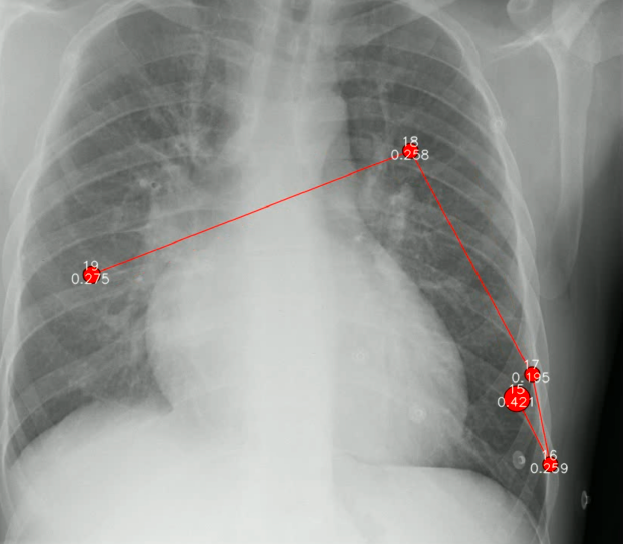

To help the research community overcome these issues, we recently published a multimodal dataset on PhysioNet which is the topic of our Scientific Data article. The dataset provides additional rich information for 1083 chest X-ray images in the MIMIC-CXR Database. Our new data consists of transcribed radiology report text, radiologist's dictation audio, and eye gaze coordinates. All these multimodal data types were collected while a radiologist read the X-ray image, with eye gaze tracked, and the dictation of the report recorded and synced with the eye gaze coordinates.

This unique dataset can help researchers build domain-expert-guided interpretable AI models. As we demonstrated in the article, we were able to produce more accurate activation maps using this data. In addition, eye-track data and the localization of the disease could be used to devise novel loss functions for training neural networks and perhaps, a deeper synergy between radiologists and AI.